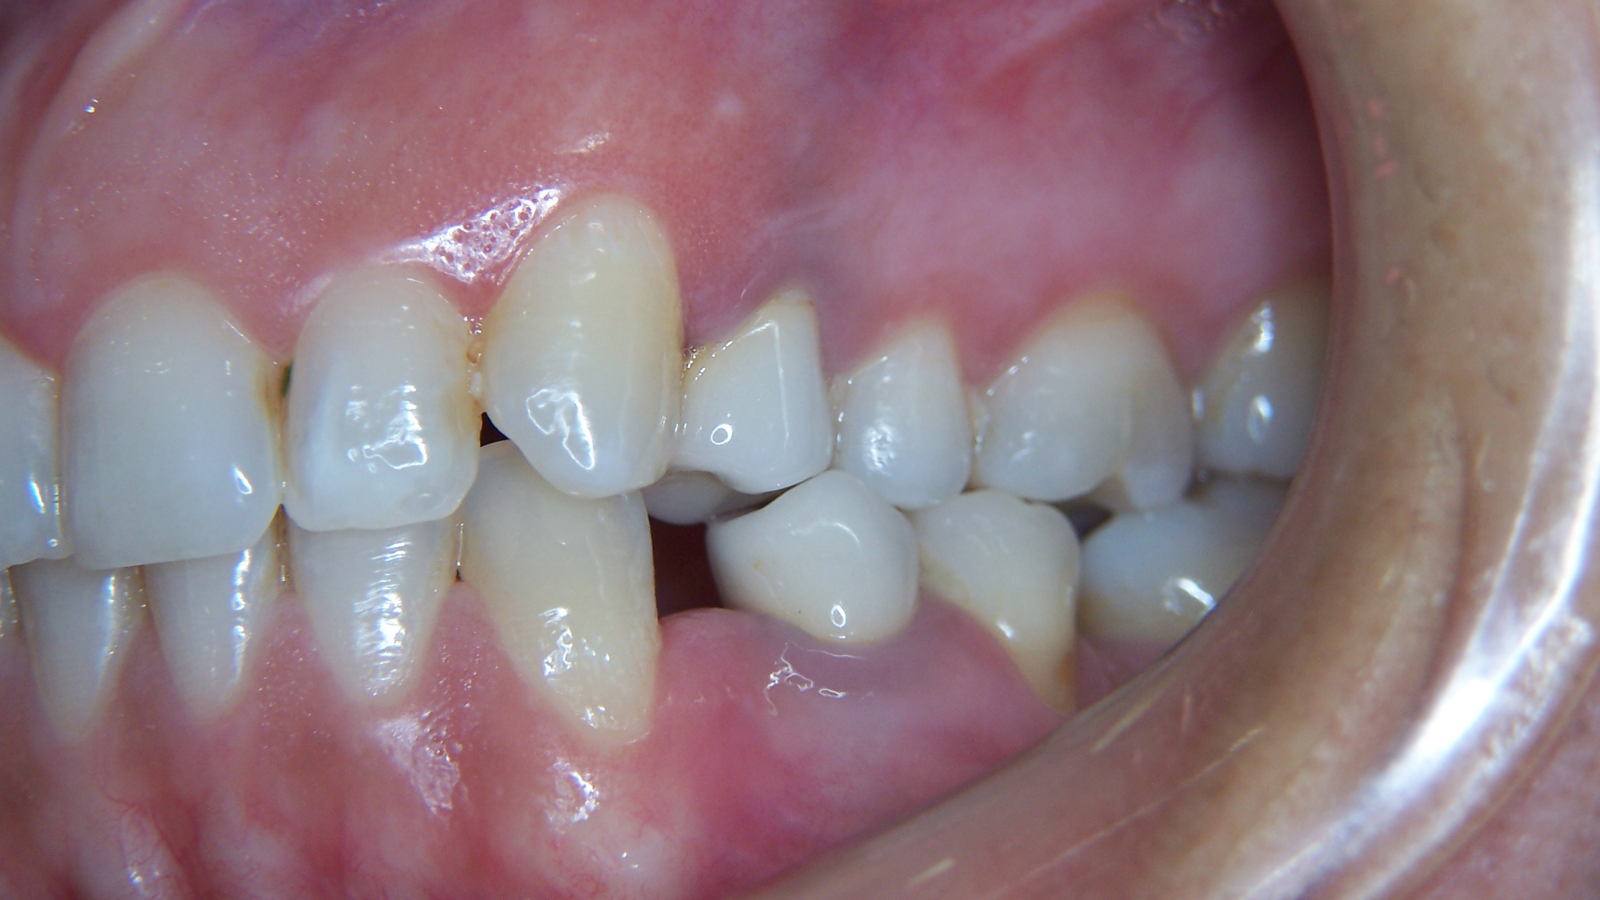

Molaire inférieure droite : infection apicale et traitement canalaire

Une jeune patiente se présente avec une infection au niveau de sa molaire inférieure droite. Sur la première image, on observe un halo grisâtre autour des sommets des racines, signe de résorption osseuse liée à l’infection.

La prise en charge a consisté en une dévitalisation réalisée en 3D, avec respect des principes essentiels : désinfection rigoureuse et maîtrise des longueurs de travail au niveau des racines.

Sur la seconde image de contrôle, le résultat est visible : disparition du halo, traduisant une évolution favorable.